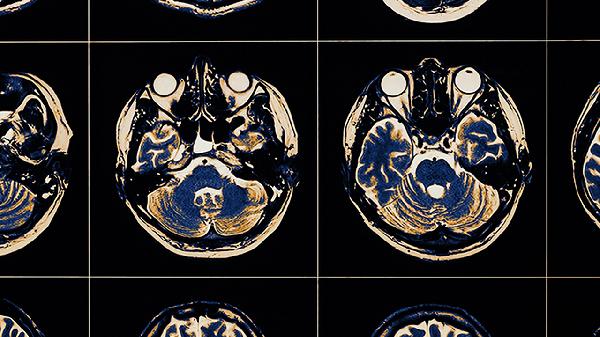

影響兒童大腦發(fā)育的行為主要有長期睡眠不足、過度依賴電子屏幕、缺乏運(yùn)動、高糖高脂飲食、忽視親子互動、過度壓力、飲水不足、不規(guī)律作息。